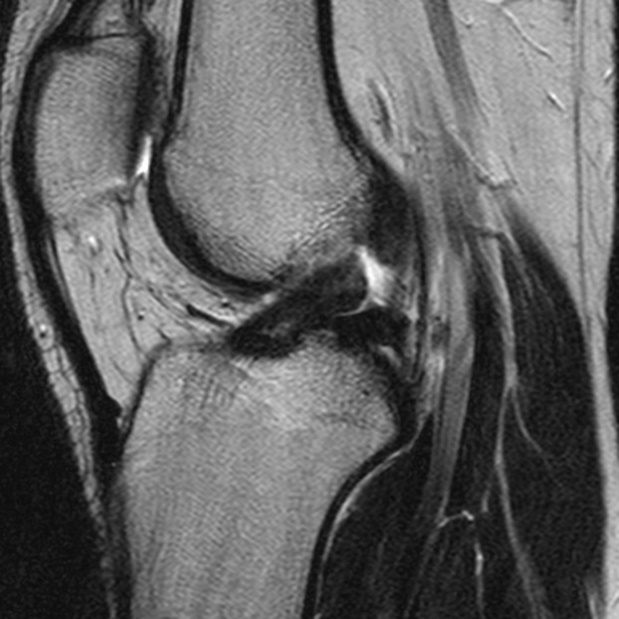

Crociato integro

Crociato Rotto

La diagnosi di lesione del legamento crociato anteriore è effettuata dall’ortopedico che, dopo aver effettuato degli specifici test ed aver studiato le immagini di Risonanza Magnetica, riesce a capire se il crociato è da operare e se sono presenti lesioni associate (danni della cartilagine, lesioni ai menischi, edemi ossei).

La Risonanza Magnetica nei casi di sospetta lesione del legamento crociato anteriore non andrebbe mai fatta prima di 10-15 gg dal trauma. Questo perché il sangue e il liquido accumulati nel ginocchio non permetterebbero una adeguata e corretta visione del legamento, rischiando di dire al paziente che il crociato è rotto quando in realtà non è così.